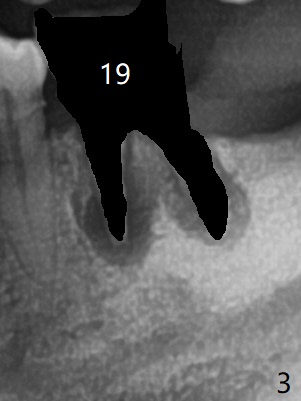

Since the distal crest is low at #19 after extraction (Fig.3), a 4.5x11 mm FC implant (Fig.4 green) will be immediately placed in the mesial socket (lingual), which has more clearance from the Inferior Alveolar Canal (yellow). Sticky bone will be initially up to the implant plateau, followed by insertion of a cemented abutment (pink), placement of the 2nd round of bone graft (red) and fabrication of an immediate provisional (white). To save time, a piece of collagen plug is inserted into the apical portion of the distal socket (blue). The distal crest will be expected to increase ~ 3 mm by the procedure mentioned above. The #32 socket heals with apparent exposure of collagen plug 2 weeks postop (Fig.5). The #27 and 28 sockets heal with fresh granulation tissue 2 weeks postop (Fig.6). The fistula buccal to #28 socket appears to have shrunken 2 weeks postop (Fig.7).